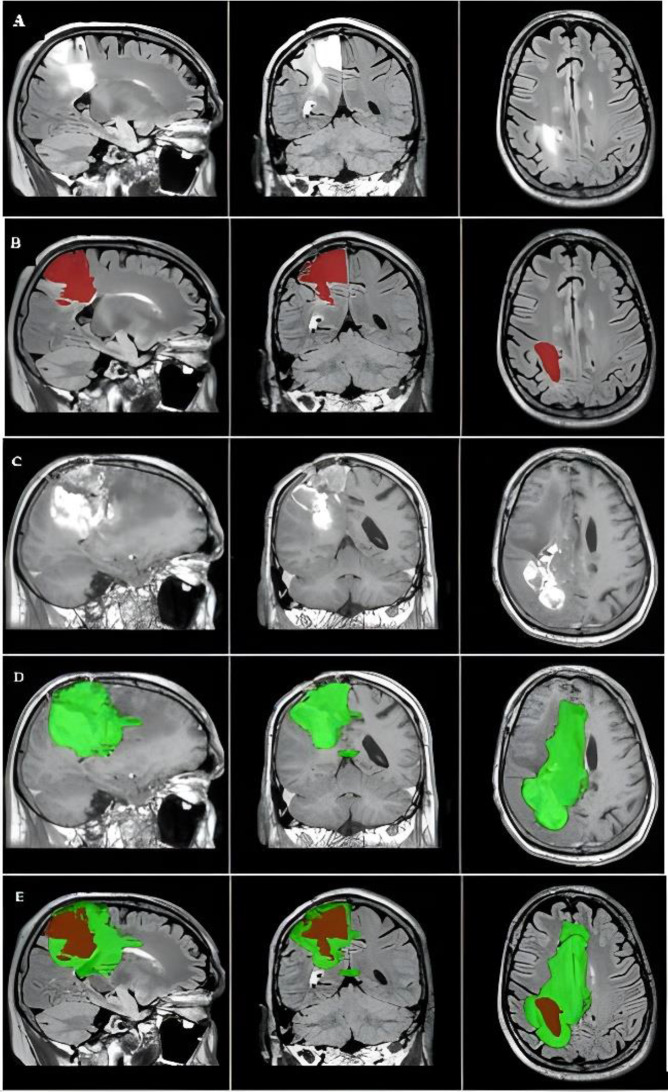

校正:术前用于鉴别胶质母细胞瘤边界的FLAIR图像。

Correction: Preoperative FLAIR images for identifying glioblastoma boundaries.